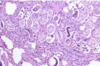

Condition

Glasser’s Disease